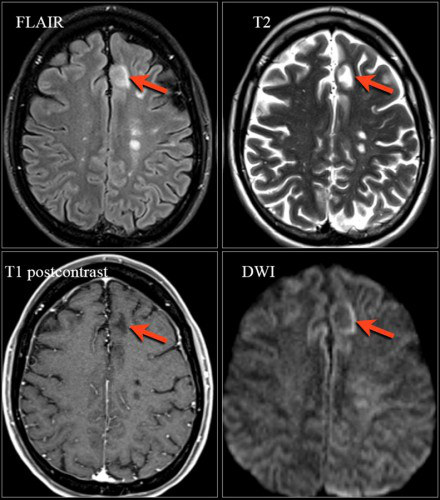

肉樣瘤

圖片十

請仔細觀察上圖并描述其病灶特點。

病灶分布與MS非常相似。除了深部白質(zhì)中有病灶,還有一些腦室周圍病灶和Dawson手指征樣的病灶。

該患者的最終診斷是肉樣瘤。

肉樣瘤的病灶特征比神經(jīng)性梅毒更像MS。

圖片十一

上圖是該患者冠狀位釓增強T1加權(quán)成像圖像。請仔細觀察上圖,我們可以看到在基底節(jié)中有點狀增強病灶,這種病灶特征可見于肉樣瘤,也可見于系統(tǒng)性紅斑狼瘡或其他血管炎性疾病。

該病例中,肉樣瘤的典型特征是軟腦膜增強(黃色箭頭所示),這是由軟腦膜發(fā)生肉芽腫性炎癥造成的。

圖片十二

該患者的另一個典型特征是線性增強病灶(上圖中黃色箭頭所示),這是由于沿著血管周圍間隙發(fā)生炎癥病變造成的,也是另一種形式的軟腦膜增強。

這些特征也就解釋了為什么肉樣瘤的病灶特征會與MS相似:血管周圍間隙與MS病變累及的小穿透靜脈相似。